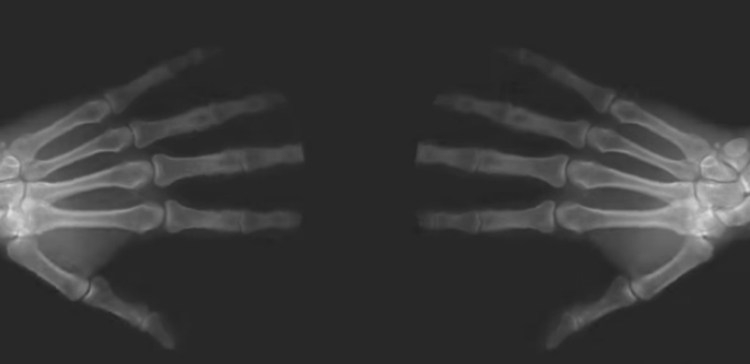

Многие исследования подкрепили это утверждение, а также 60-летней эксперимент, выполненный и описанный исследователем Дональдом Л. Угером. В течение шести десятилетий, этот преданный человек только трещал костяшками на одной из его рук, в то время как он никогда не трещал ими на другой руке. Он делал это, чтобы увидеть, будет ли на одной руке развиваться артрит больше, чем на другой руке.

После 60 лет растрескивания на одной руке, Угер имел одинаковый артрит на обеих руках, по существу, доказывая, что образование треска не влияет на ваши суставы отрицательно или положительно, на самом деле.